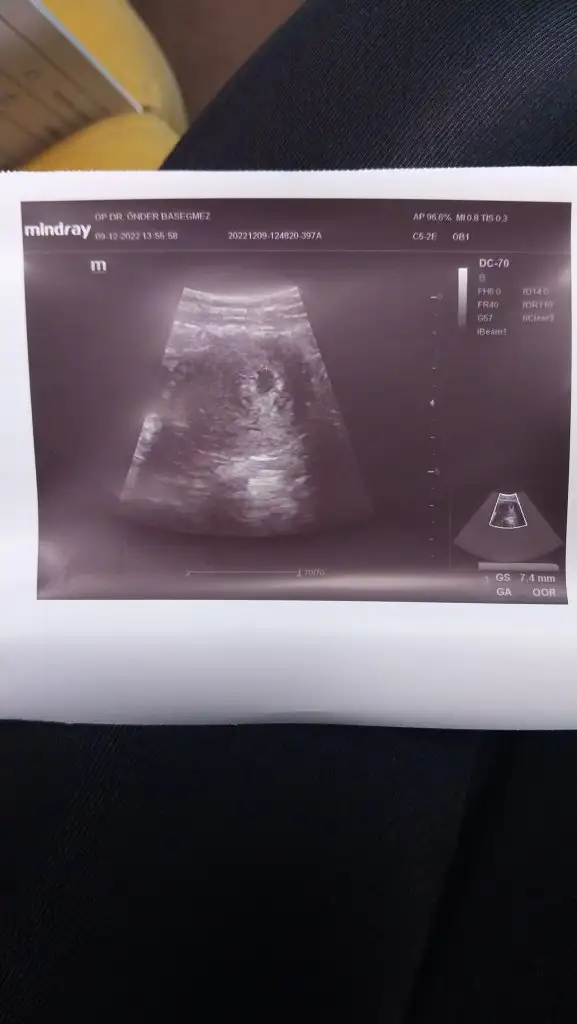

Aaa bende önder başeğmez e gidiyorum. Yani bugün ona ilk gidişimdi. Aa tesadüfKuzucugum ekledim bu arada sen de Adana dasin kime gidiyorsun doktora? Ben şimdi doktordan geldim Önder bey e gidiyorum. Kesem iki katına çıkmış 9 mm olmuş teyzesi23 üne kalp atışı için çağırdı

Sağ altta yaziyor canım7.4mm nerede yazıyor acaba ultrason kagıdında

Bende başkalarınınkini görmeye başladım ama kendiminkini görmüyorum . Profil<forum seçenekleri<başkalarının imzalarını gör gibi bişey dediler canım ona izin verince görünüyor herkesinkiYaa o altta kaç haftalık gebe olduğumuzu gösteren şey bende de çıkmıyor kızlar, keşke çıksa ama![]()